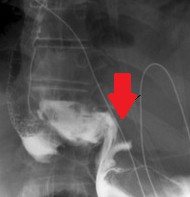

Οισοφαγοστομία. Αποκλεισμός κατώτερου οισοφάγου (Ευγενική παραχώρηση Dr. V. Penopoulos)